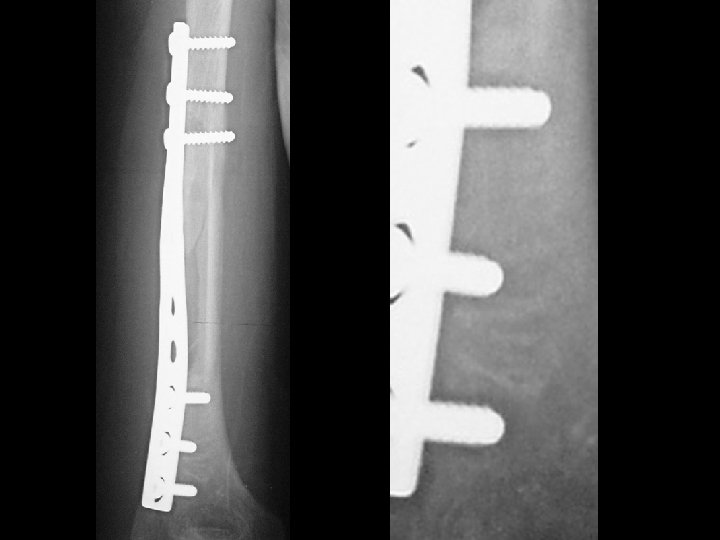

Hardware infection • Findings: – 2 mm lucency surrounding fixation hardware and screws • ddx: – Hardware loosening